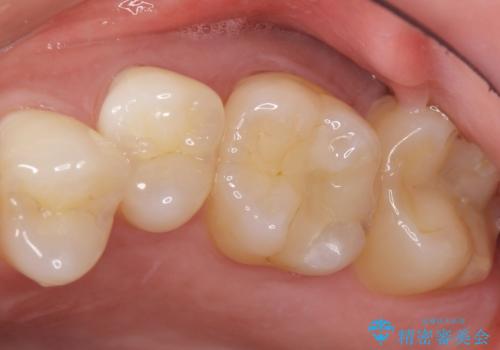

奥歯にフロスを通すと臭い 30代女性

- 奥歯にフロスを通すとにおいがすることを気にされ、来院された患者様です。

精査したところ、奥歯に充填された保険内のコンポジットレジンの適合が悪いことにより、汚れがたまりやすい状態でした。

不適合なレジンを除去し、セラミックインレーによる治療を行いました。(右上76左上67右下7の計5本)